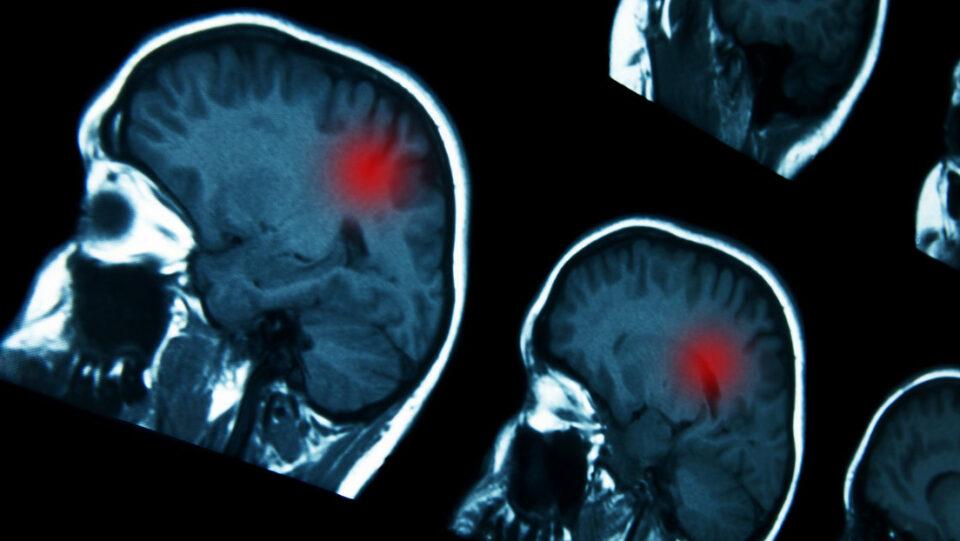

Internacional, 28 de mar 2024 (ATB Digital).- El uso prolongado de ciertos progestágenos, fármacos hormonales que se usan para tratar trastornos ginecológicos, se asocia a un mayor riesgo de desarrollar un tipo de tumor cerebral conocido como meningioma intracraneal, según un estudio publicado este miércoles en la revista médica The BMJ.

Así, se concluyó que el uso prolongado (un año o más) de medrogestona se asoció a un riesgo 4,1 veces mayor de padecer meningioma intracraneal que requiriera cirugía, mientras que el uso prolongado de acetato de medroxiprogesterona inyectable se asoció a un riesgo 5,6 veces más alto, y el uso prolongado de promegestona se relacionó con un riesgo 2,7 veces mayor. Sin embargo, no parece existir tal amenaza si estos progestágenos se utilizan por menos de un año.